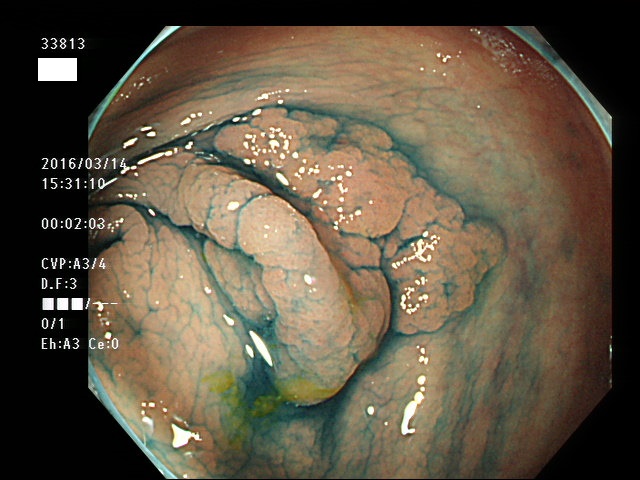

上記100名より抽出した平坦・陥凹型腺腫(=癌化の危険が高いが見落としやすい病変)の内視鏡写真